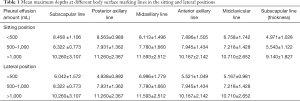

Each surface marking of the maximum depths of pleural effusion in sitting and lateral positions is shown in Table 1. The pleural fluid total protein was detected, and if the total protein was greater than 25 g/L, the fluid was an exudate. If the protein was less than 25 g/L, the fluid was a transudate. Among all patients, 68 patients had exudates and 30 patients had transudates, and the detailed results of US examinations are shown in Table 2.

Full table

Full table